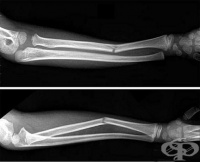

S52 Счупване на костите на предмишницата

Заболявания

Счупване на костите на предмишницата могат да се класифицира в няколко групи според различни критери...

S52.4 Съчетано счупване на диафизите на лакътната и лъчевата кост

Счупване на костите на предмишницата са едни от най-често срещаните. Механизъм на съчетано счупване ...